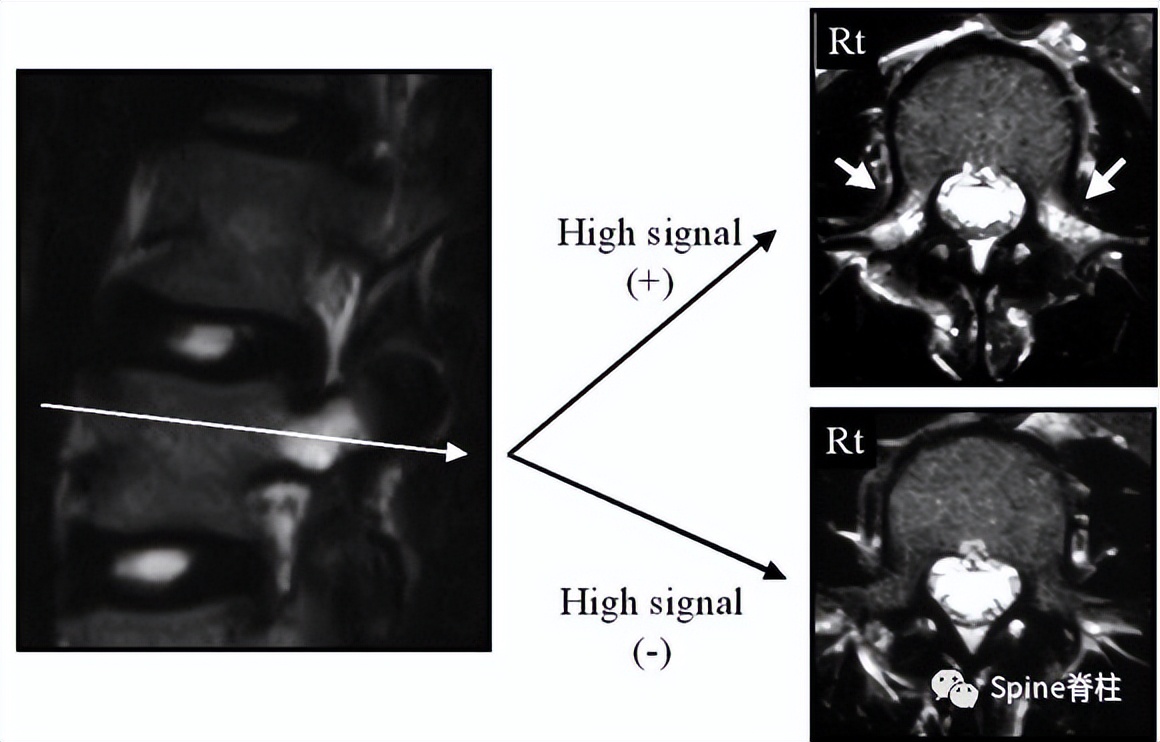

有研究发现磁共振上 椎弓根出现T2高信号改变是青少年和儿童峡部裂的早期诊断征象 。同时, 存在椎弓根高信号改变也是保守治疗后能达到骨性愈合的良好预测指标 (也就是说存在T2椎弓根右高信号改变的峡部裂患者,其峡部裂经保守治疗愈合的可能性大) 。

右上图为椎弓根高信号改变(+),右下图为(-)

Sairyo教授研究发现磁共振上 椎弓根出现T2高信号改变是青少年和儿童峡部裂的早期诊断征象 。同时,存在椎弓根高信号改变也是保守治疗后能达到骨性愈合的良好预测指标(也就是说存在T2椎弓根右高信号改变的峡部裂患者,其峡部裂经保守治疗愈合的可能性大)。

图:右上图为椎弓根高信号改变(+),右下图为(-)

右图提示椎弓根高信号改变(箭头)

右图提示双侧椎弓根高信号改变(箭头)

右图:右侧椎弓根高信号改变明显,左侧椎弓根轻微高信号